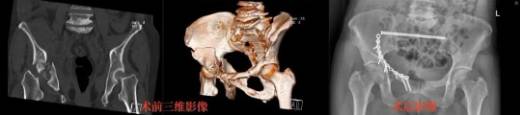

人体骨骼如高楼钢筋,骨盆位于中心,承上启下。骨盆髋臼骨折手术因难度极高、风险极大,被称为骨科“黄金冠手术”。

56岁的王女士不慎从15米高处坠落,骨盆多发粉碎性骨折,伴创伤性休克。传统手术需前后路大开刀,极易损伤神经血管,风险巨大。

多学科会诊后,团队决定采用目前最先进的入路方式,通过骶骨骨折闭合复位螺钉固定和经腹直肌旁入路髋臼骨折复位。

手术中,骨科团队展现了扎实的手术功底,仔细解剖,凭借精湛技术精准操作,历经2小时,顺利完成骨折复位及固定,术后,患者恢复良好,疼痛减轻、活动范围增加,配合康复治疗和锻炼,髋关节功能得到有效恢复。